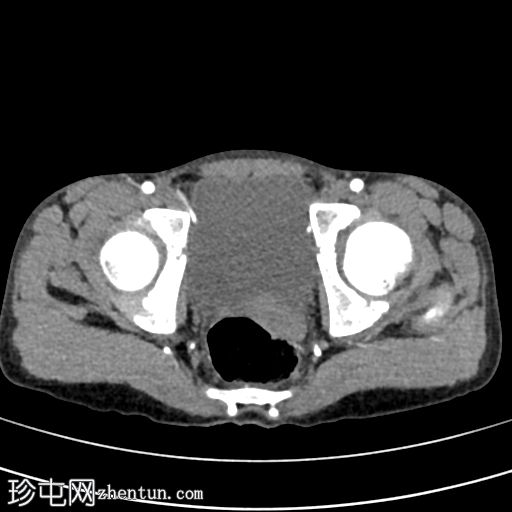

轴位增强扫描(延迟期)

3.jpg

脾脏显示弥漫性实质损伤(根据美国创伤外科协会(AAST)脾脏损伤分级标准,为IV级损伤)。脾脏实质内可见一灶性造影剂聚集,提示脾内出血而非脾外出血。

腹腔内可见轻度高密度液体,符合血腹表现。

左侧可见轻至中度胸腔积液。

影像学表现符合IV级脾脏损伤。